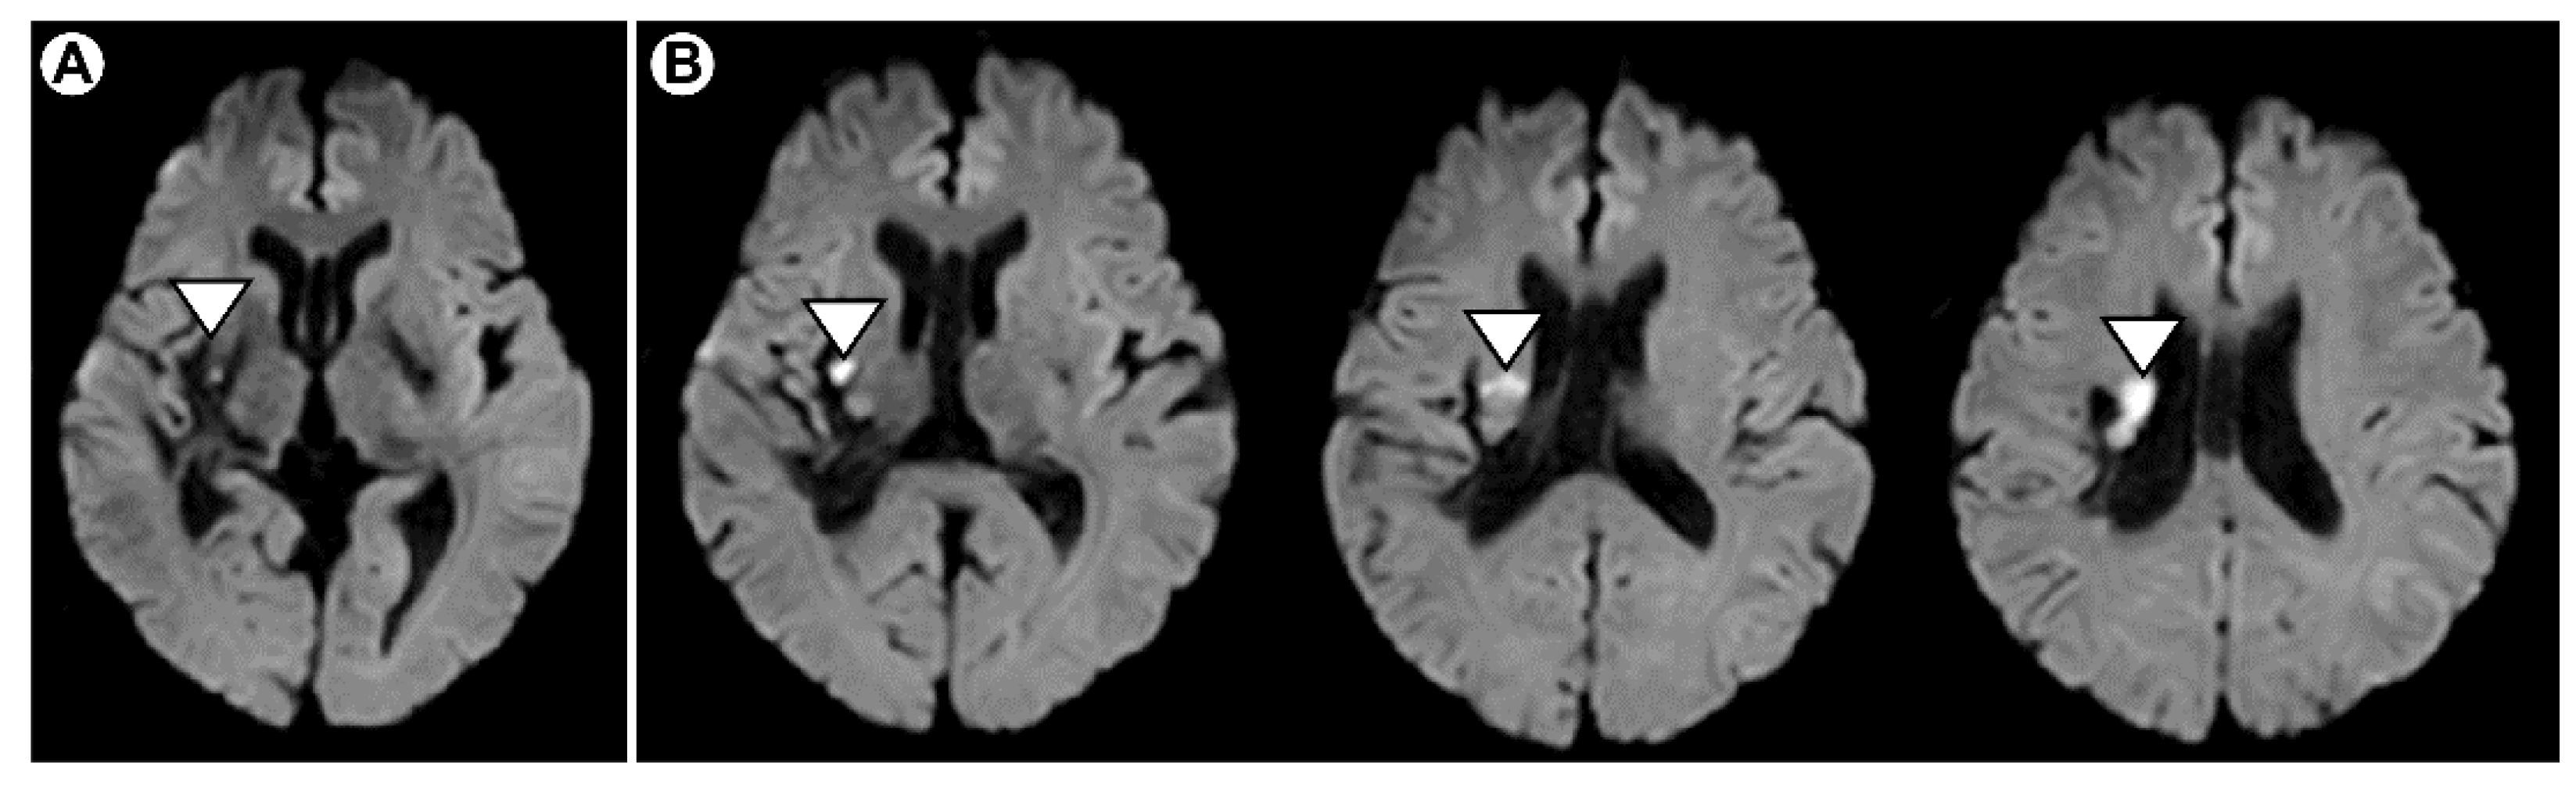

2.1. Case Introduction